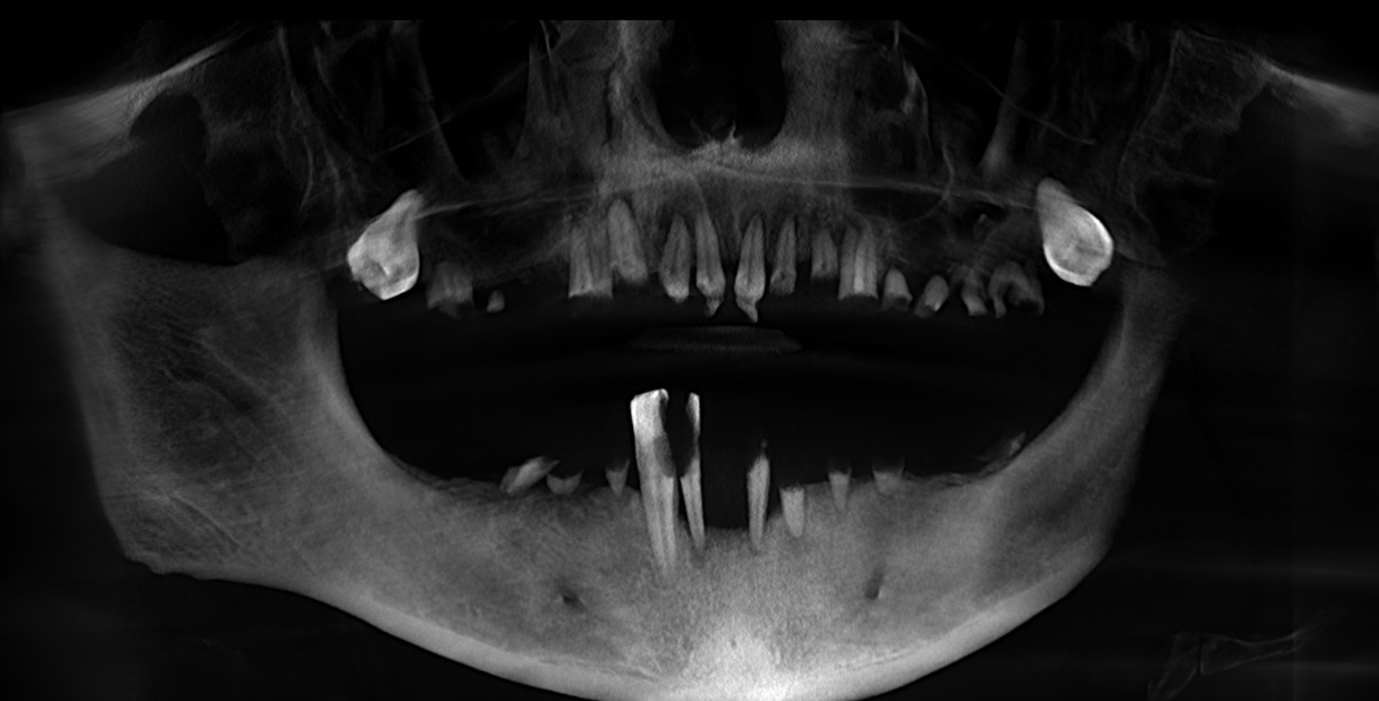

We completed a full clinical examination and took detailed records, including:

• clinical photographs

• intraoral photos

• OPG x-ray

• CBCT scan

• digital implant planning records

These records helped us carefully assess bone levels, gum health, and implant positions.

xAlthough the patient had moderate bone loss in some areas and signs of old chronic abscesses, his overall bone quality was still suitable for implants. There was no active pus or severe infection at the time of treatment.